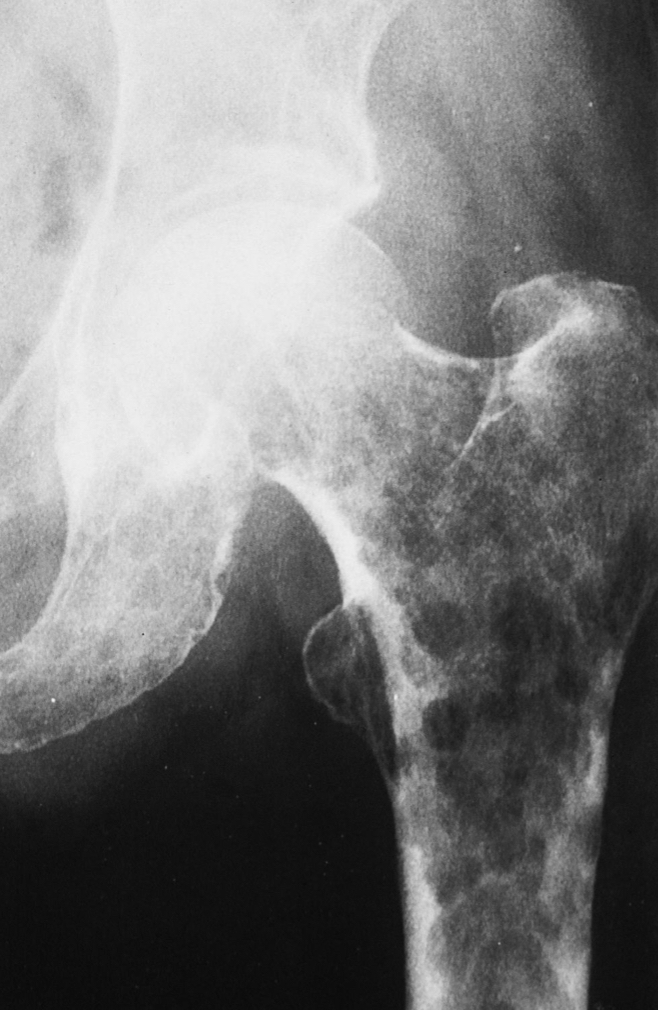

what is the ddx list for this?

what is this?

polyostotic fibrous dysplasia (FD)